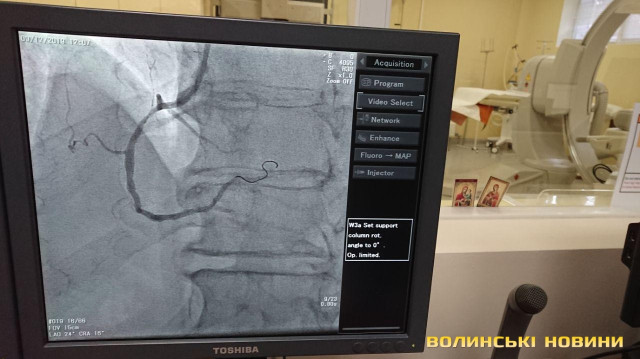

З 2013-го року реперфузійні центри працюють за системою «24/7», тобто ми допомогу надаємо у будь-який час і кожного дня. З 2018 року до цієї роботи долучився реперфузійний центр у м. Ковель завдяки ангіографу, встановленому за кошти субпроекту Світового банку. У нашому центрі щодня маємо 3-5 процедур. Також почали проводити тромбоекстракцію у пацієнтів з ішемічним інсультом. Це складна процедура, яку роблять у небагатьох клініках України. Суть у тому, що при інсульті треба вчасно відкрити судинку. У судину заводиться спеціальне обладнання і проводяться маніпуляції із видалення тромбу. Є випадки, що молодим людям ставало значно краще.